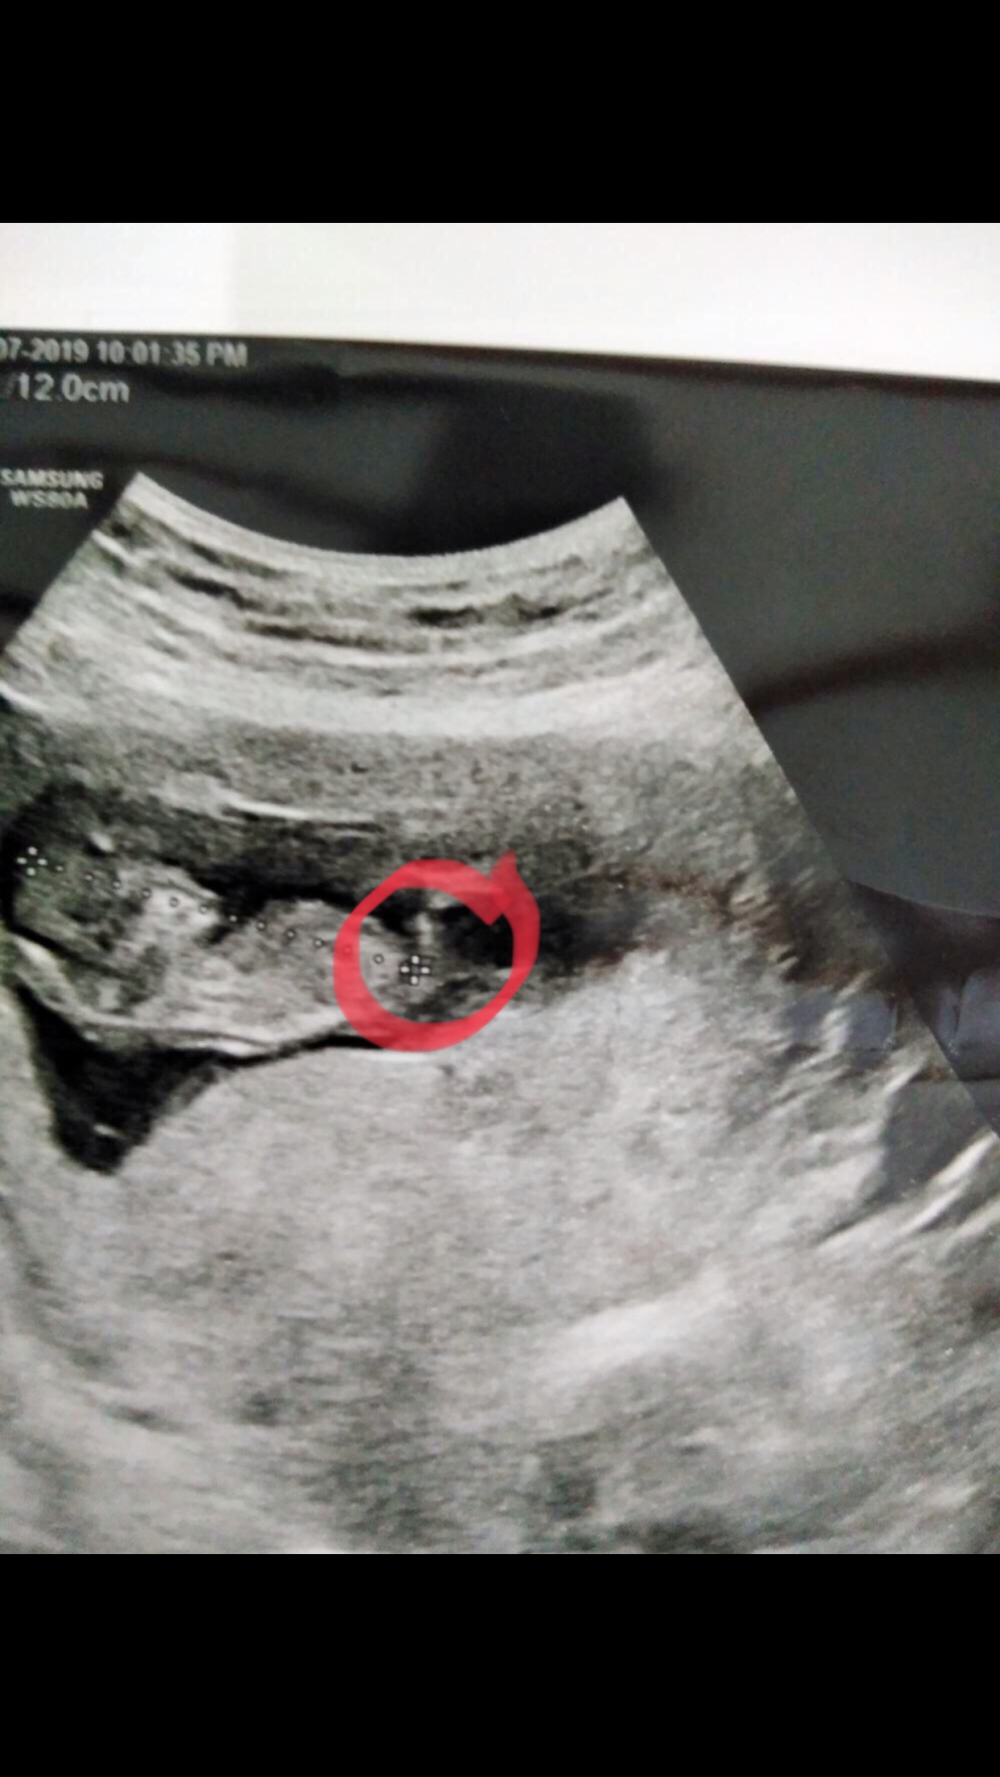

خبيرات السونار في وني بجنس الجنين بالأسبوع ١١

من خلال نظرية الناب اذا ارتفع ولد واذا نازل بنت